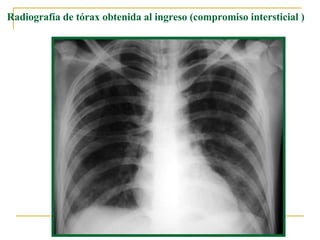

Radiografía de tórax obtenida al ingreso (compromiso intersticial   )

Radiografía de tórax control a los 5 días del ingreso (opacidades tipo “vidrio esmerilado” )